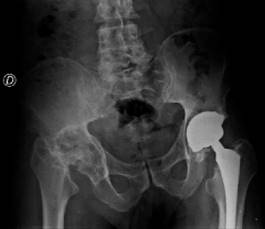

Se realiza radiografía anteroposterior (AP) de pelvis donde se observa pérdida de la esfericidad de la cabeza femoral, presencia de osteofitos, esclerosis con colapso subcondral, disminución del espacio articular, todo compatible con cambios degenerativos avanzados que se acompañan de cambios acetabulares secundarios a la osteonecrosis. En la cadera izquierda se observan componentes protésicos acetabular y femoral adecuadamente colocados y orientados, sin datos de interfaz, lisis o aflojamiento (Figura 1). Para identificar adecuadamente la morfología femoral y acetabular, se toma tomografía computarizada donde se aprecian múltiples quistes subcondrales, así como defecto óseo contenido, con pérdida considerable de hueso esponjoso principalmente de la pared posterior (Figura 2).

Figura 1: Radiografía anteroposterior de pelvis en la que se observa cadera derecha con colapso de la cabeza femoral, abundantes osteofitos, datos de esclerosis y presencia de quistes subcondrales. La cadera izquierda se observa con material protésico adecuadamente colocado, sin datos de rotura ni fatiga.